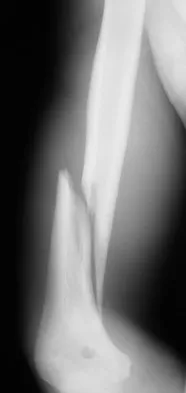

A 30-year-old man has pain in the left arm after a motor vehicle accident. His neurovascular examination is intact, and radiographs are shown in Figures 25a and 25b. What is the best course of management?

Explanation